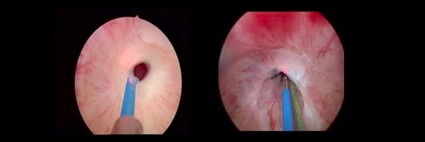

Estenosis de uretra:

La estenosis de uretra consiste en un estrechamiento a nivel de conducto de la orina que comunica la vejiga con el exterior, si la estenosis trae repercusión en el paciente se considera que debe ser tratada y el método con el cual se realice se decide según la localización y longitud de la misma. En caso de optar por el tratamiento endoscópico, esto se realiza mediante un instrumento denominado uretrotomo que lleva un cuchillete con la finalidad de cortar el área estenótica, para su uso se requiere pasar este instrumento a través de la uretra sin embargo en ciertas circunstancias el pasaje de este instrumento está contraindicado (por ejemplo pacientes con esfínter artificial por incontinencia), por lo cual se puede realizar la uretrotomía con instrumentos más finos y empleando el láser para realizar el corte de la estenosis.